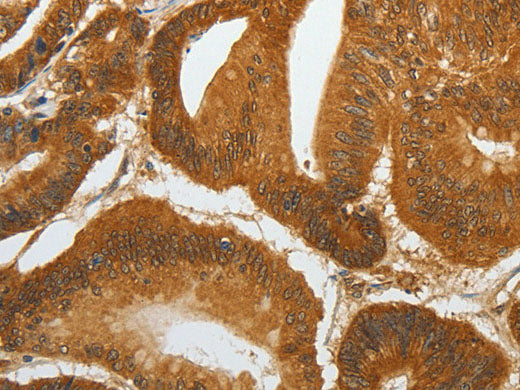

RETNLB Polyclonal Antibody Reactivity Human

Reactivity Human

Host Rabbit

Applications IHC

Applications Recommended Dilution

IHC 1:50-1:200